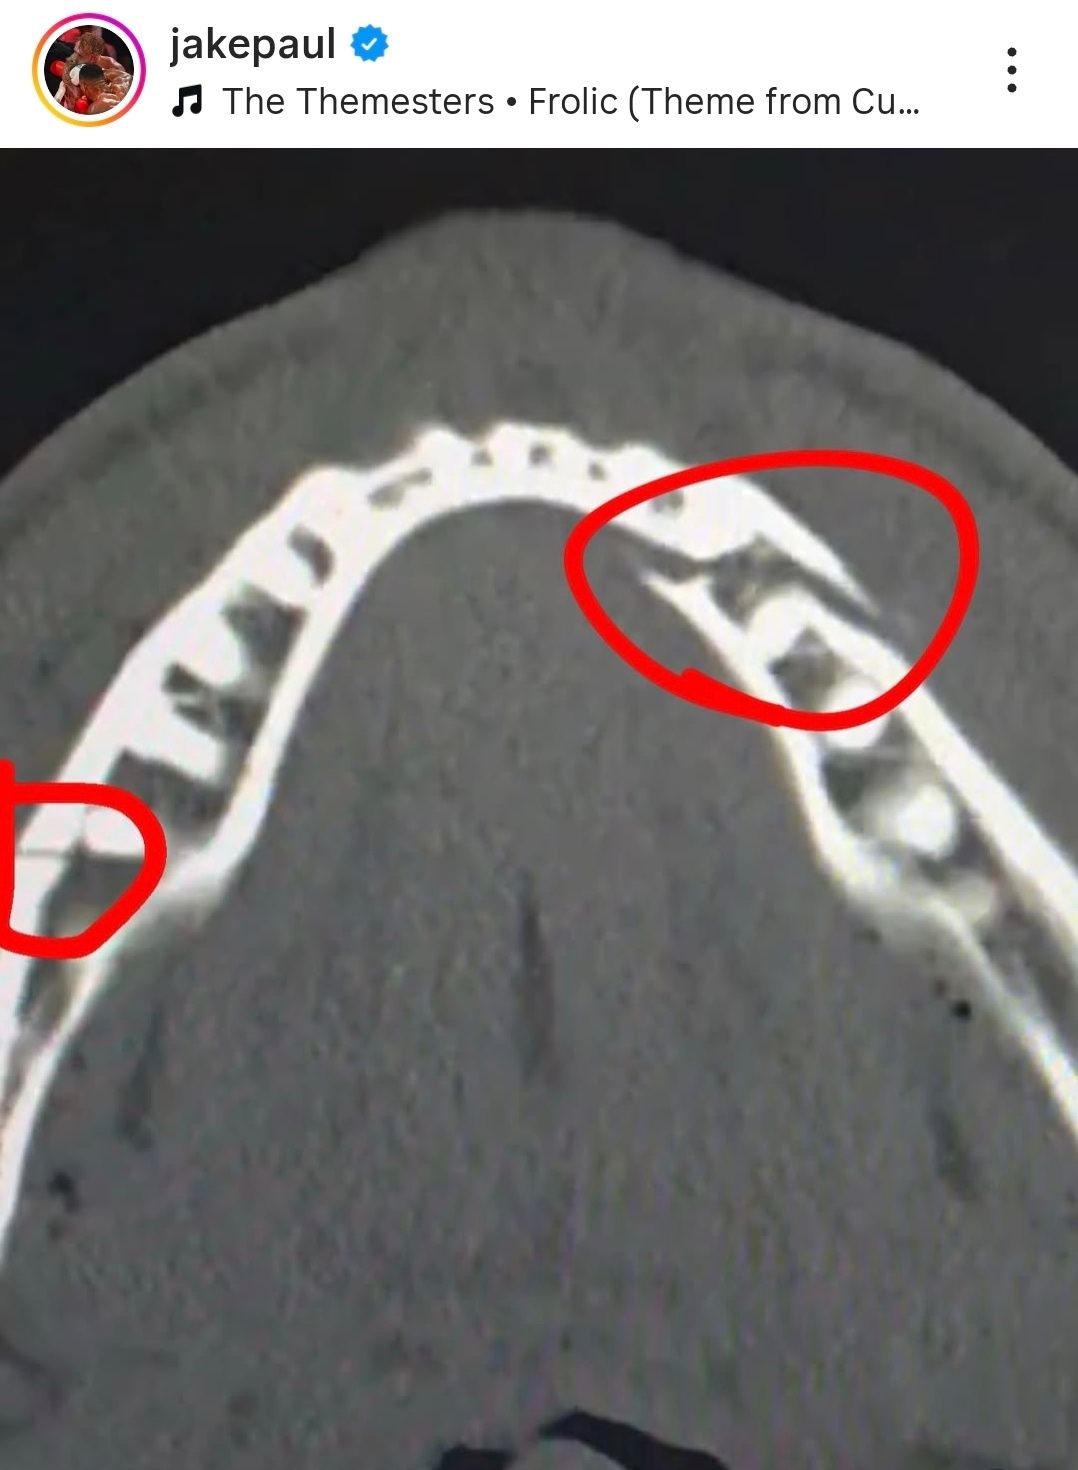

元世界ヘビー級王者のアンソニー・ジョシュア選手(36、英国)とのイベントマッチで6回KO負けを喫したユーチューバーのジェイク・ポール選手(28、米国)が、顎の骨を2か所骨折する重傷を負った。

ポール選手は21日(現地時間)、Instagramに顎のX線画像を投稿し、骨折したことを明らかにした。病室で撮影した写真も添え、「応援してくれてありがとう。私は大丈夫だ」と近況を伝えた。さらに「10日後にカネロ(サウル・アルバレス)と対決させてほしい」と冗談めかして書き込んだ。

その後の追加投稿では、手術が順調に終わったと報告し、「痛みが強く、体がこわばっている」と説明したうえで、「7日間は流動食だけで過ごす」と記した。

試合は前日、米フロリダ州マイアミのカセヤ・センターで行われた。ジョシュア選手が主導権を握り、ポール選手から計4度のダウンを奪った。6ラウンドには強打が顎に直撃し、倒れたポール選手は立ち上がろうとしたものの体勢を立て直せず、レフェリーが試合を止めた。